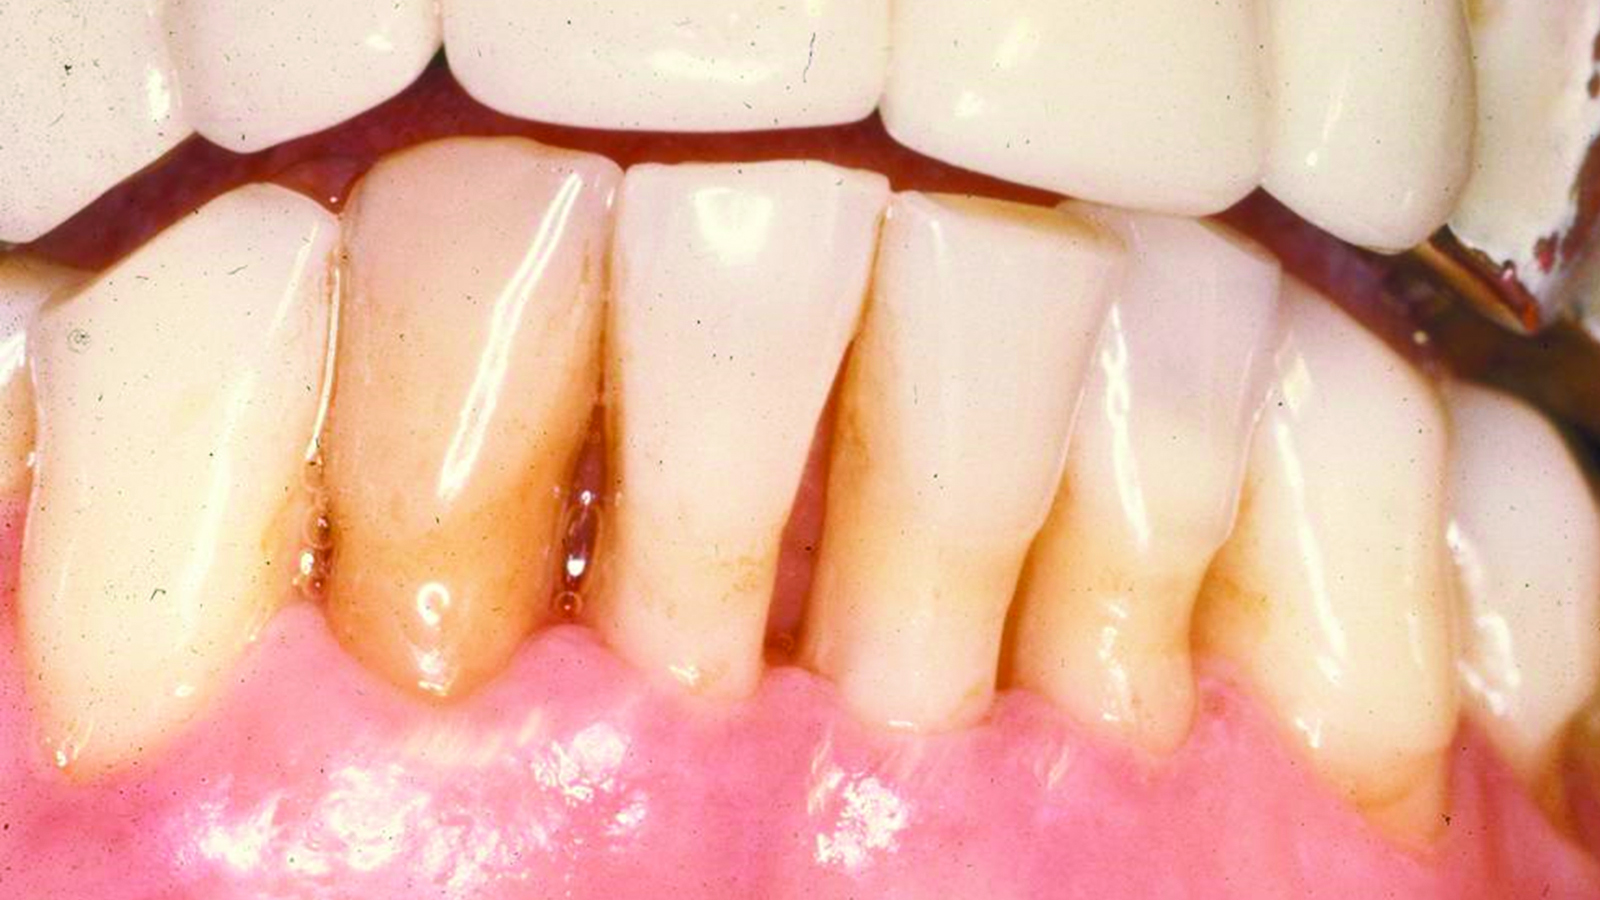

Fig 6. Results of SRP demonstrated resolution of inflammation and residual probing depths of 2 mm to 3 mm, 18 years after treatment of Case 1 patient.

Figure 6

Fig 9. SRP resulted in the elimination of inflammation and remaining probing

depths of 2 mm to 3 mm in Case 2 patient, 3 months post-therapy.

(Fig 4 through Fig 9 are courtesy of Dennis Tarnow, DDS.)